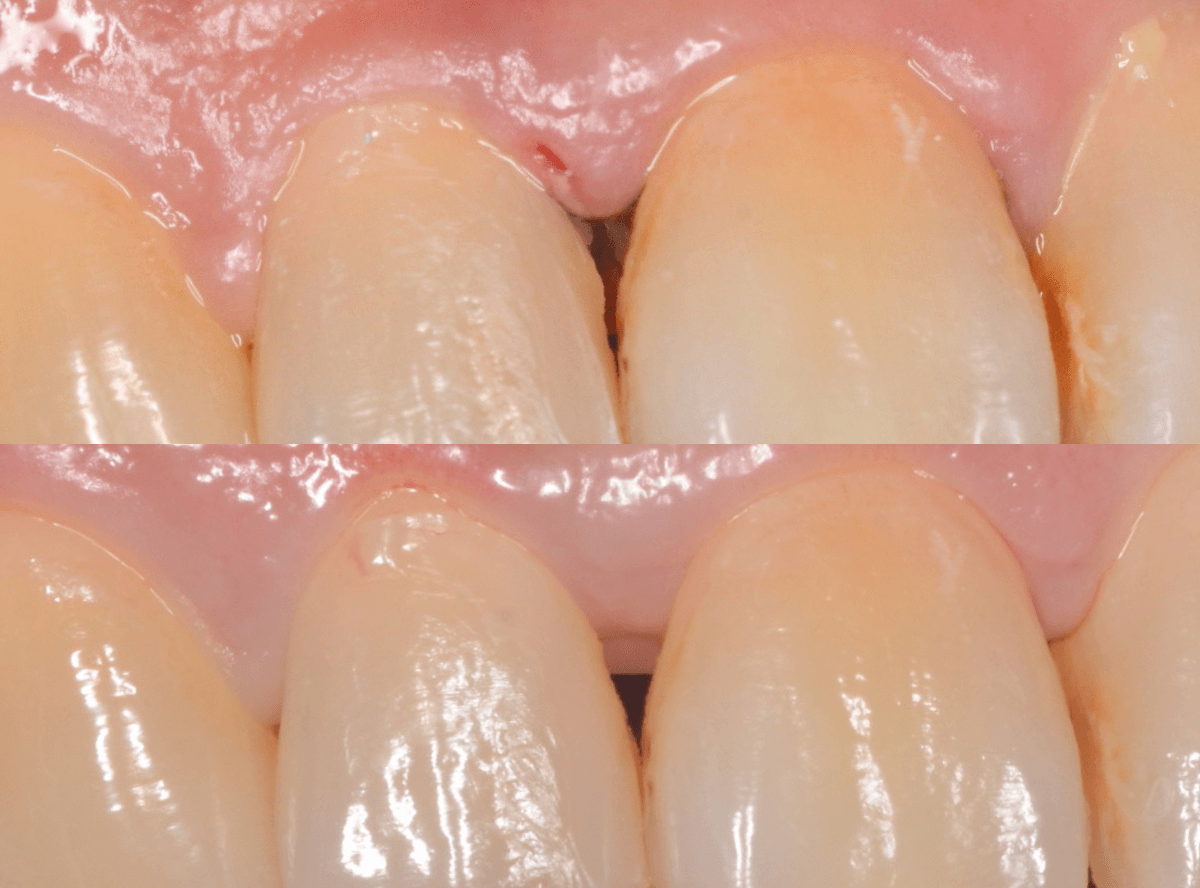

その後、この患者さんは熱心に通院とお手入れをされて、約二か月が経ちました。

歯肉は順調に引き締まってきました。

歯周治療は、ご本人のメンテナンスなしには結果が出ません、頑張ってらっしゃる形が見えて、とても嬉しいですね

こちらが比較写真です。

並べてみると、治り具合がよりわかりますね